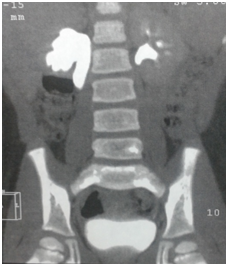

5 year old boy came to our outpatient department with intermittent flank pain since one week. There were no other systemic complaints. Patient was previously investigated & operated for right non palpable testis a year ago. An incidental finding of right mild hydronephrosis (AP Diameter of 12mm) were noted during sonological evaluation. General and systemic examination were normal. Haematological workup was normal. Ultrasonography showed hydronephrosis with antero-posterior diameter of 3.5cm associated with dilatation of upper ureter (dia-9.2 mm). Micturating cystourethrogram was done to rule out vesico ureteric reflux. DTPA renal scan was suggestive of preserved parenchymal function & GFR with significant subrenal obstruction at right peviureteric junction along with upper hydroureter. CT-IVP demonstrated right hydronephrosis with dilatation of the upper ureter due to kinking at junction of upper & middle ureter suggestive of obstruction (Figures 1&2). Left kidney was normal.

Figure 1 CT IVP image.